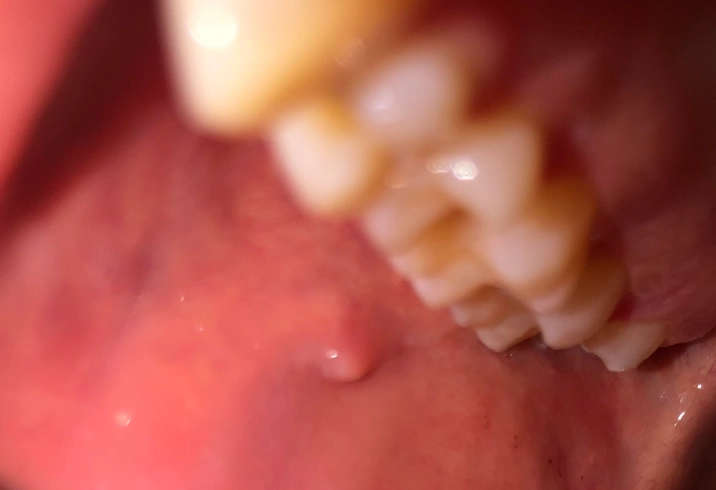

This is probably the champion of painless oral bumps. A mucocele is a tiny, fluid-filled sac that forms when a small salivary gland duct gets blocked or damaged (often from accidentally biting your cheek or lip). It's like a little blister of saliva trapped under the surface. What it feels/looks like: It's usually soft, smooth, and bluish or translucent. It can appear to change size, sometimes shrinking and then filling up again. You'll commonly find it on the inner lip, the floor of the mouth (where it's called a ranula if it's larger), or the inner cheek. It's completely painless but can be annoying.